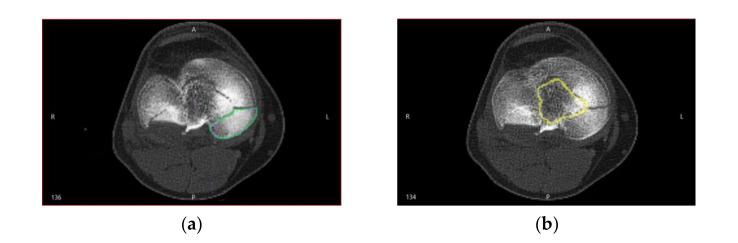

The planning of the surgical treatment in orthopedics, with the help of three-dimensional (3D) technologies, arouses an increasing scientific interest. Scientific literature describes some semi-automatic reconstructive attempts at fragmented bone fractures, but the matching algorithms presented are likely to improve. The aim of this paper is to develop a new method of aligning fragments of comminutive fractures. We have created a structured integration process and an alignment algorithm integrated in a clinical workflow for personalized surgical treatment of fractures. The provided solution is able to align the surfaces of bone fragments derived from the segmentation process of volumetric tomographic data. Positional uncertainties are eliminated interactively by the user, who selects the corresponding pairs of fracture surfaces. The final matching and the right alignment are performed automatically by the innovative alignment algorithm. The paper solves a challenging problem for the reconstruction of fractured bones, namely the choice of the optimal matching option from the situation in which surface portions of a fracture fragment correspond to multiple high fragments. The method is validated in practice for preoperative planning of a 49-year-old male patient who had a tibial plateau fracture of Schatzker type VI.

摘要